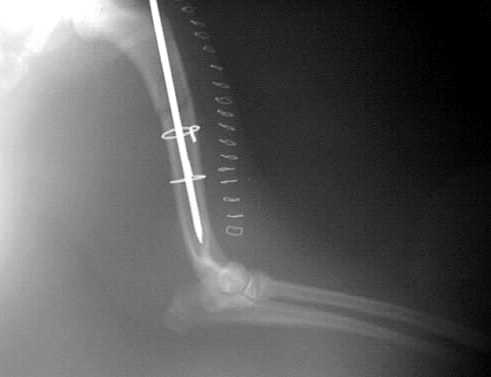

Oberarm-Trümmerfraktur

Marknagelung